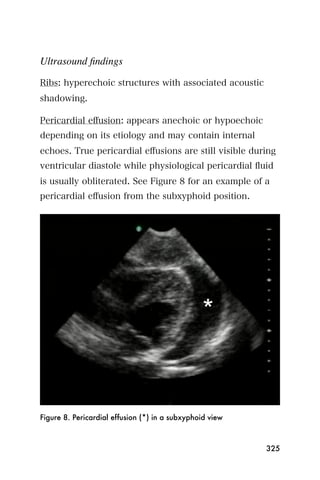

The subxyphoid four-chamber view is used to examine

for pericardial effusion. A pericardial effusion is found

by looking for an anechoic stripe around the heart

within the parietal and visceral layers of the pericardial

sac. Pleural effusions are anechoic stripes found

cephalad to the hyperechoic diaphragm.

A pericardial effusion will appear as an echo-lucent

(black) area between the heart and the thin white stripe

of the pericardium, as shown in Figure 16.

Figure 16. Subxyphoid view showing a pericardial effusion

As mentioned, if the pericardial effusion has more

inflammatory debris, as in a pericardial effusion related

to tuberculosis, the pericardial effusion may appear

more gray or echo-dense.